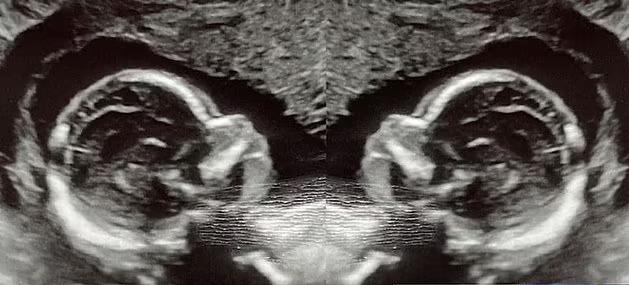

وفي ربيع هذا العام، علمت الأم لثلاثة أطفال أنها حامل بتوأم من البنات، ومع ذلك فقد صُدمت عندما علمت خلال الفحص الأول بالموجات فوق الصوتية أنها تحمل طفلًا واحدًا في كل رحم.

وقال الدكتور ريتشارد ديفيس، من مستشفى جامعة ألاباما- برمنجهام، إن الرحم المزدوج نادر بحد ذاته، وأن وجود توأم في كل منهما يمثل فرصة واحدة في المليون، وأن احتمال وجود توأم في كل منهما أمر جنوني حقًا.